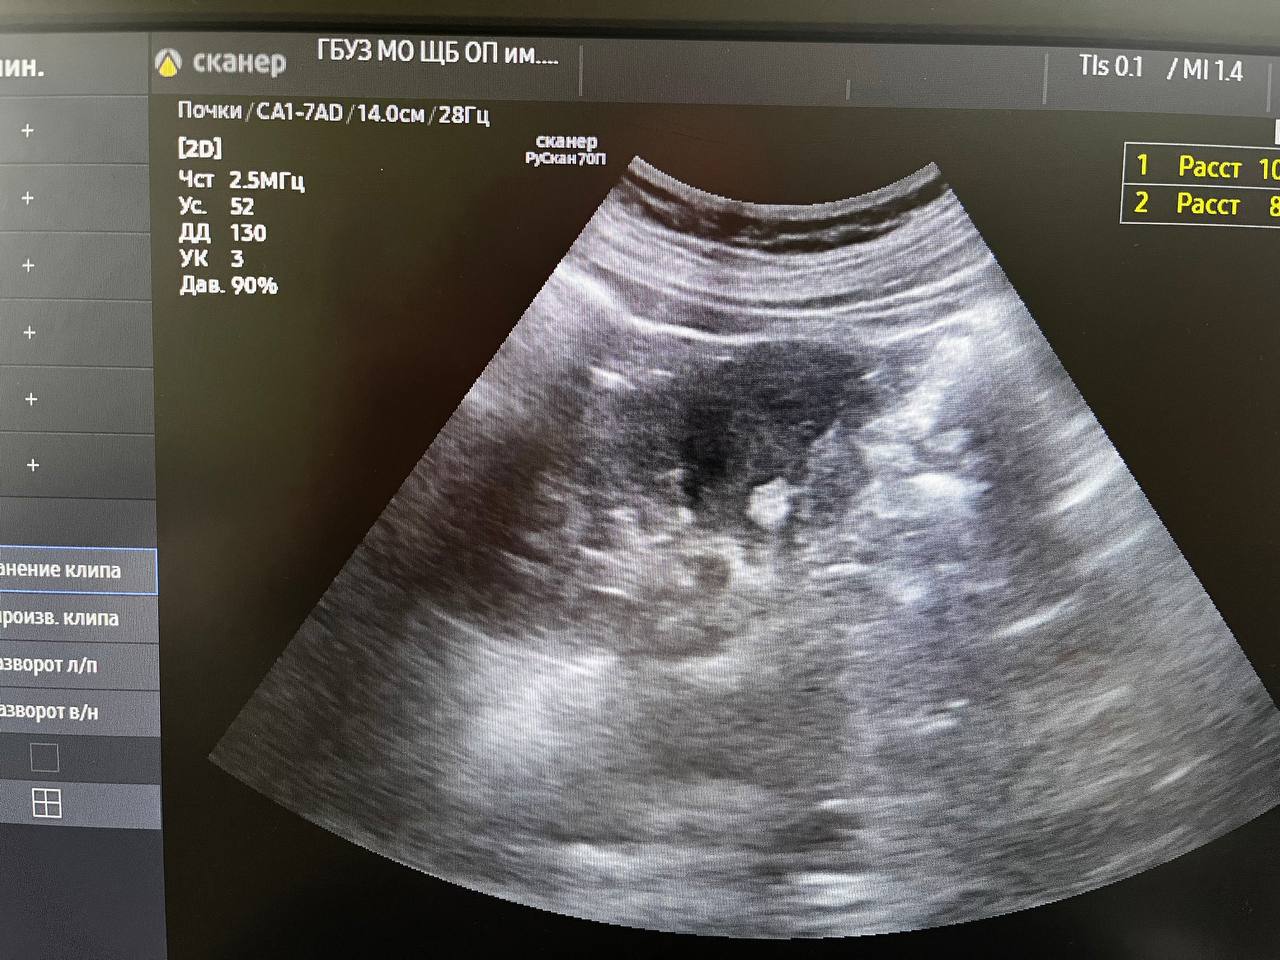

В минувшую субботу в день здоровой почки проверить своё здоровье пришли 22 человека. У двоих из них выявлены серьёзные патологии при полном отсутствии жалоб. Остальные пациенты были с мелкими кистами почек до 10мм и "песочком". Всем выполнено УЗИ, выданы направления на лабораторные обследования. Так же были пациенты без патологии, пришедшие для комплексного обследования со стороны мочевыделительной системы, выполнено УЗИ, выданы направления на общий анализ мочи "У одного пациента - мочекаменная болезнь, чашечные камни с обеих сторон до 15мм. Направлен на МСКТ для установления точной локализации и положения камней с целью подготовки для плановой госпитализации и оперативного лечения. У второго пациента выявлено образование в правой почке до 12мм. Пациент направлен на МСКТ для верификации", - уточнил врач-уролог поликлиники для взрослых обособленного подразделения им. М.В. Гольца Щёлковской больницы в г. Фрязино Владимир Орленко Щёлковская больница проводит тематические дни открытых дверей на регулярной основе, благодаря чему жители городских округов могут проверить своё здоровье без ожидания свободной записи к узким специалистам. |